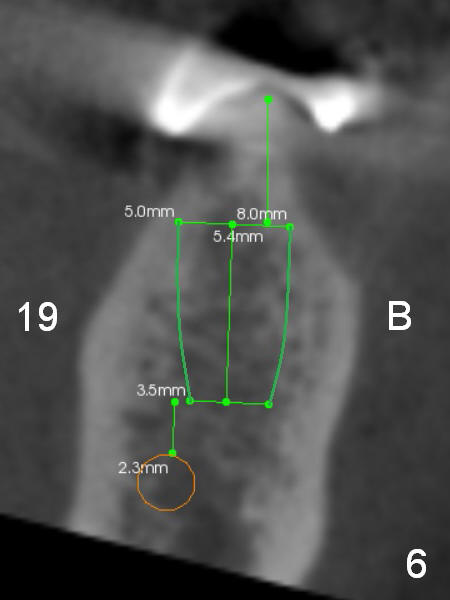

A 69-year-old man would consider implant option for his upper front teeth (Fig.1: #5-9) if there is no separate bone graft procedure. He does not want implants for his lower left molars (#18,19), since he has had a partial denture. In fact the bone at #5-9 is so thin that 2-3 mm 1-piece implants can be placed at #5,7 and 9 (Fig.2-5 (CT coronal sections (B: buccal)) for a 5-unit bridge (Fig.1). To support and increase the longevity of the latter, implants at #18,19 are mandatory (Fig.6,7).

Wheel saws will be used to split the ridge before drilling at #7 (Fig.4). Surgical bur is to be used for ridge reduction prior to osteotomy at #19 (Fig.6), while at #18, osteotomy depth will be 10 mm for 8 mm implant (Fig.7).